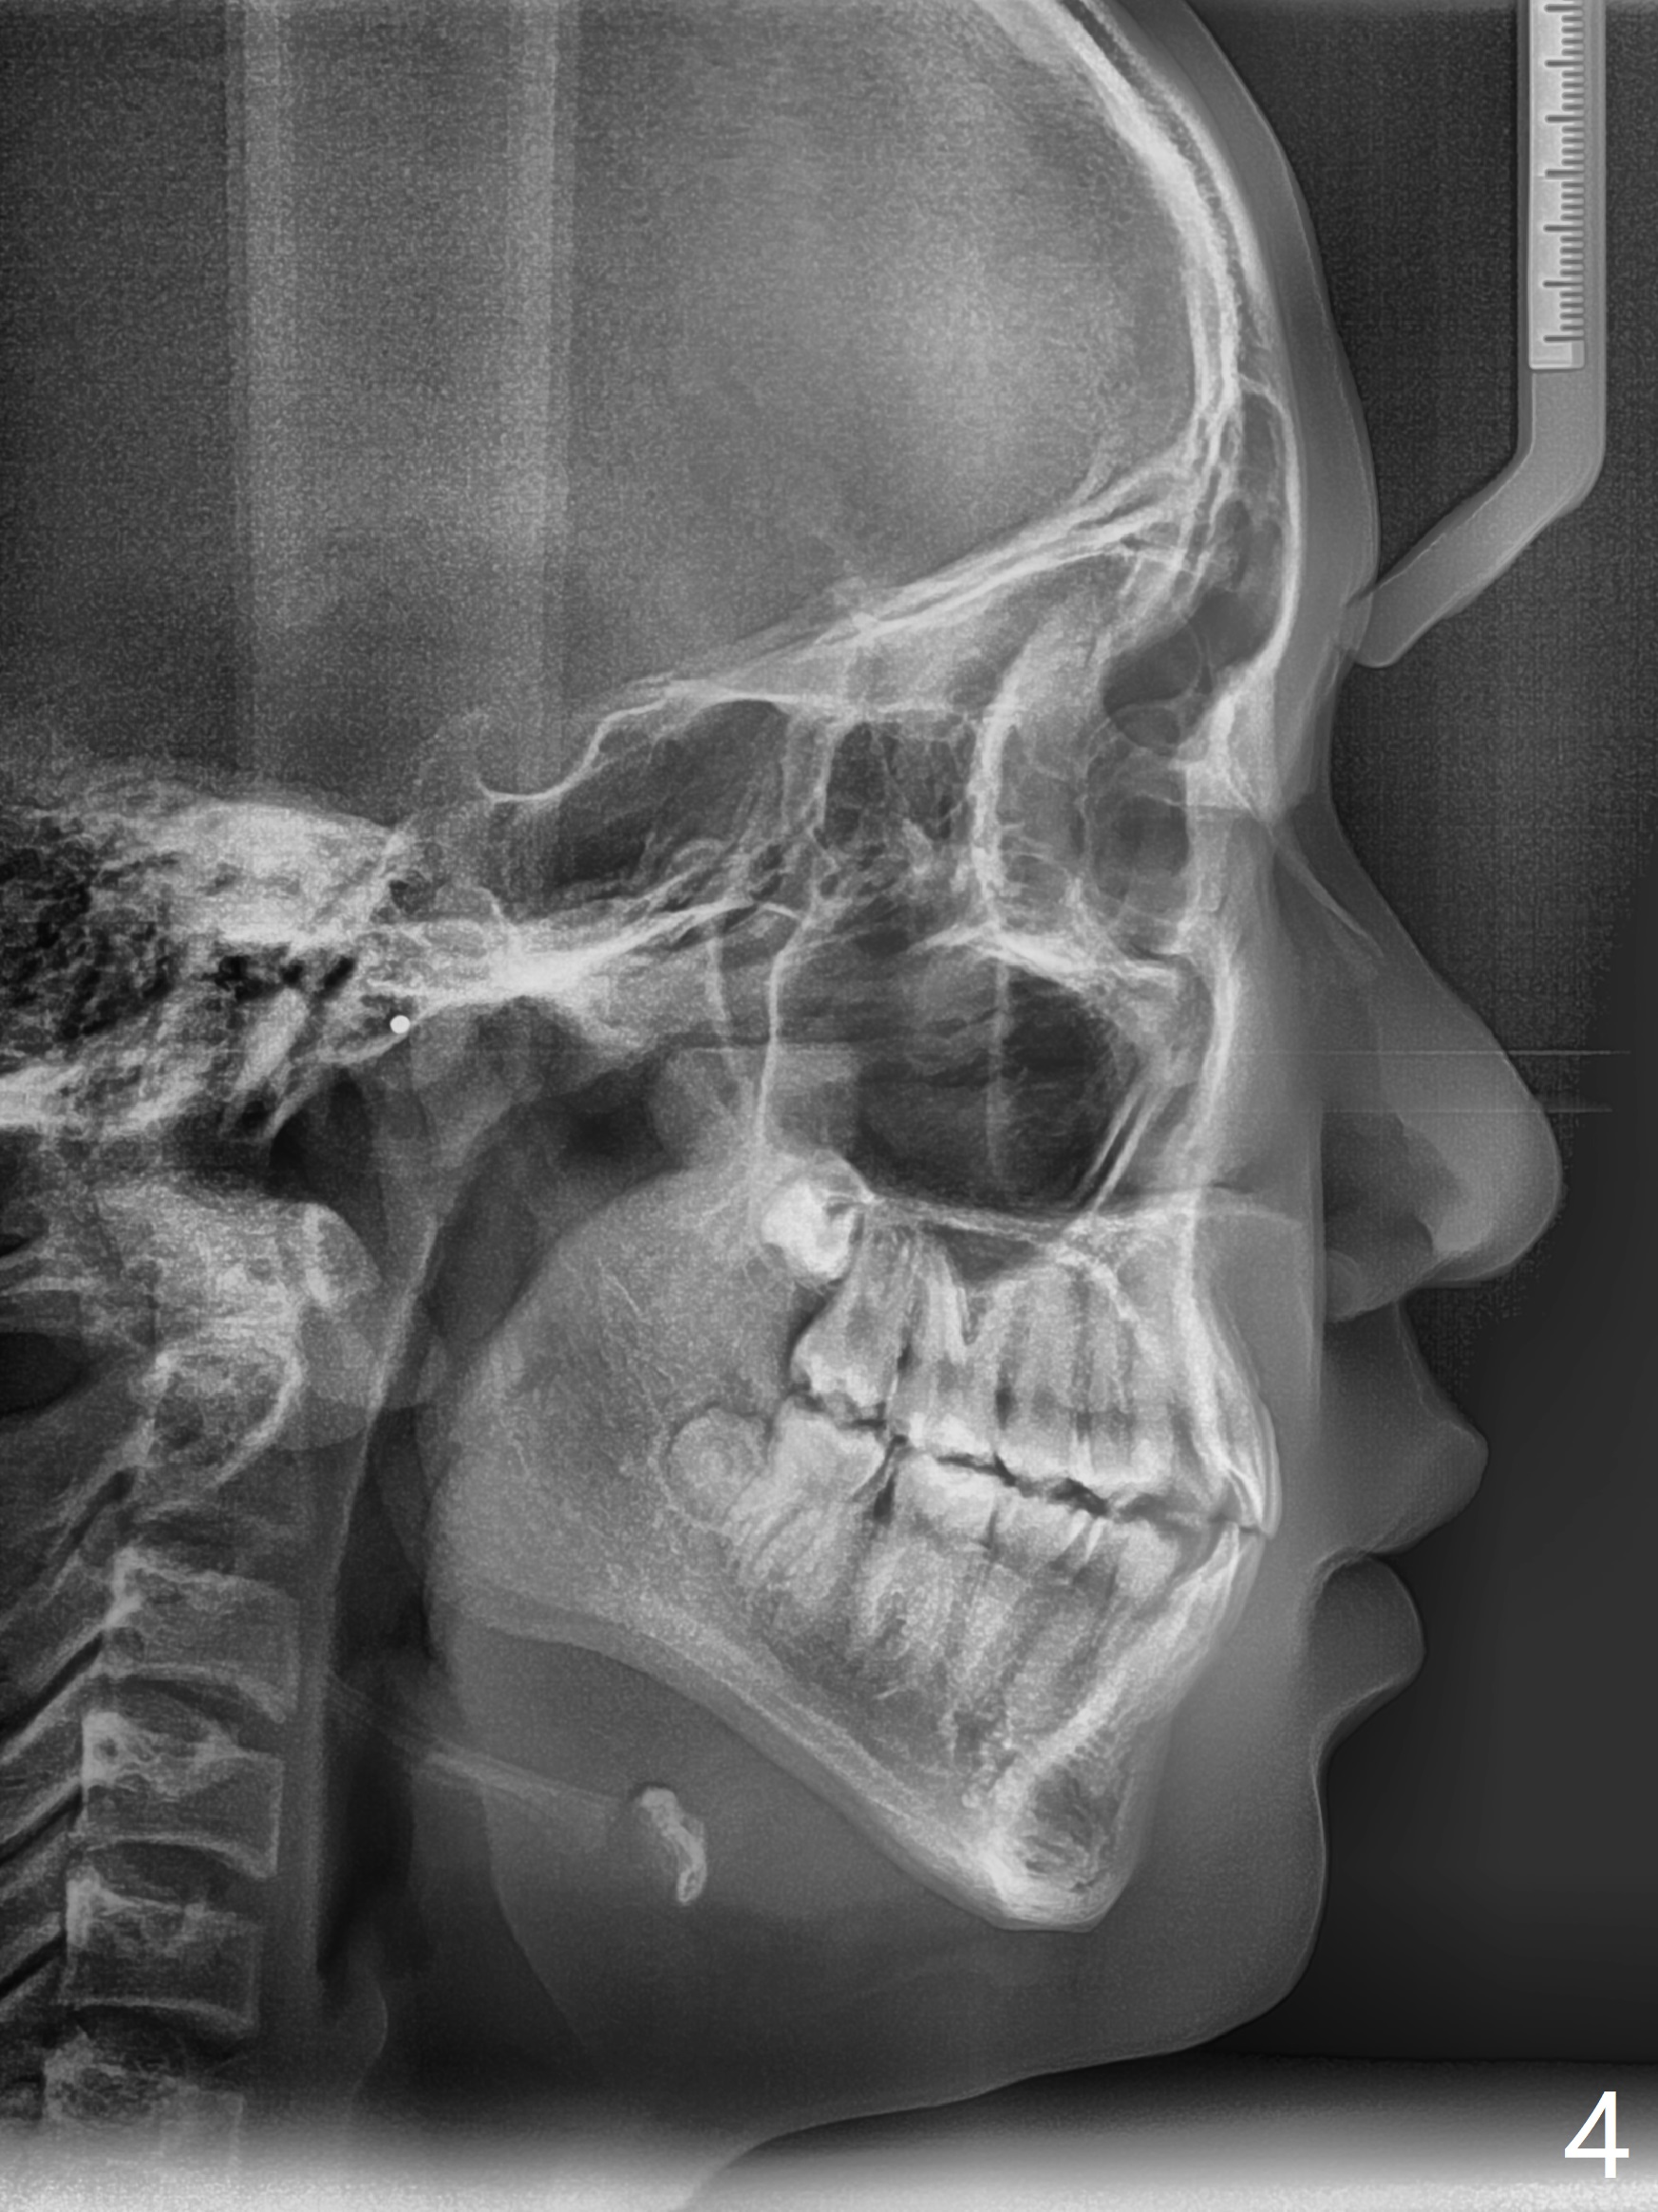

A 14-year-old man requests ortho because of crowding lower anterior and UR missing lateral (Fig.1-4). Open space for the future implant at UR2 will correct upper midline deviation (Fig.1) and change Class II malocclusion to I on the right (Fig.6, as compared to Fig.7). To control UR1,3 root torque, bracketing on these 2 teeth will be intentionally off (Fig.5). The treatment will take ~ 2 years. Prior to implantation at UR2, what type of prosthesis should be made?